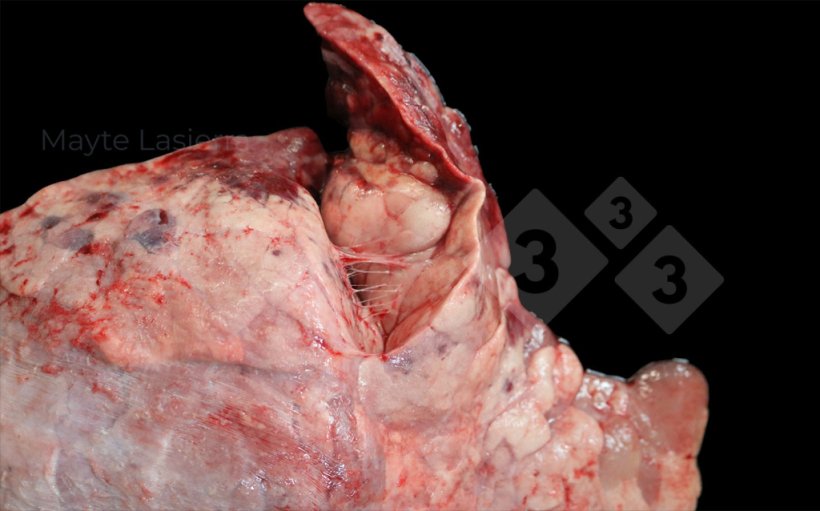

Zapalenie opłucnej występuje często i obejmuje zmiany chorobowe w dogrzbietowo-doogonowej części płuca, związane głównie z podostrą lub przewlekłą postacią zapalenia opłucnej świń (APP). Objawia się białymi plamami na opłucnej trzewnej płatów przeponowych, odpowiadającymi złogom włóknika.

Zapalenie opłucnej może również występować w obszarach doczaszkowych płuc, powodując zrosty między sąsiednimi płatami płucnymi. Zazwyczaj towarzyszą mu koinfecje pochodzenia bakteryjnego (Pasteurella multocida, Glaesserella parasuis, Streptococcus suis itp.) i nazywane są zapaleniem opłucnej doczaszkowej, aby odróżnić je od zapalenia opłucnej związanego z APP.